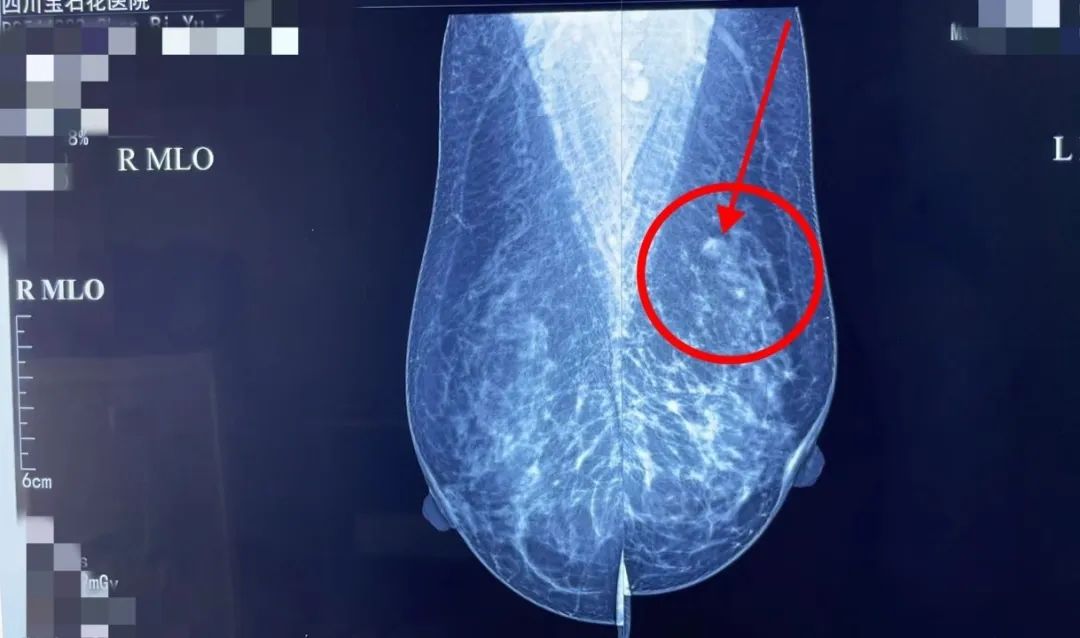

结合吴女士多年的检查情况,陈波建议她做一个钼靶检查,起初她不太愿意,认为乳房超声检查没有大问题,就不需要做钼靶了。在陈波主任的详细介绍和耐心劝说下,最终做了钼靶。钼靶检查发现左乳外上象限仅5毫米形态规则无钙化灶结节,结合多年诊疗经验,陈波为吴女士进行了保乳手术治疗,术后病理结果提示为浸润性癌。